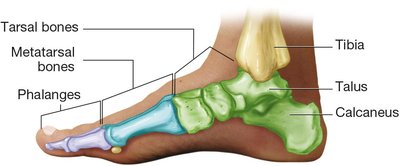

Leg, Ankle, and Foot

The femur joins the tibia to support body weight. The fibula is the smaller bone of the lower leg. The patella protects the knee joint. The tarsal bones in the ankle connect to the metatarsal bones in the foot, and each toe contains three phalanges (except the great toe, which has two).

Bones of the lower extremity including femur, tibia, fibula, patella, and foot bones Bones of the foot including tarsals, metatarsals, and phalanges